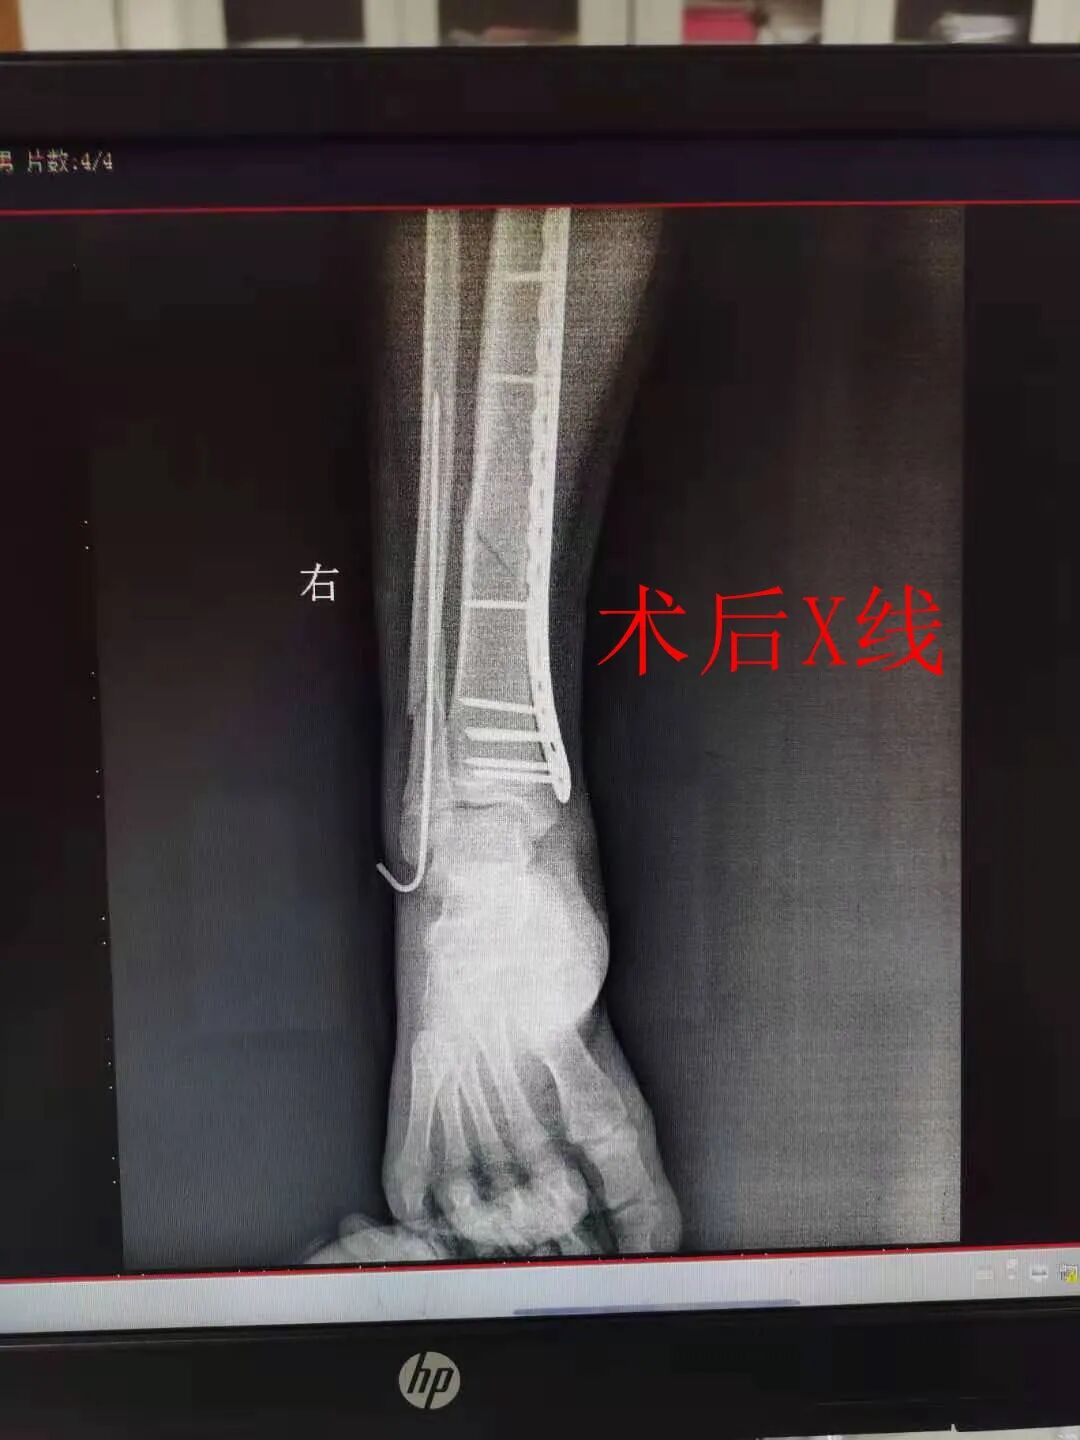

外二科副主任,2009年毕业于福建中医药大学骨伤系。曾于厦门大学附属福州第二医院创伤科、足踝外科进修。擅长于四肢骨折、颈肩腰腿痛、髋关节病、膝关节病等骨科各种常见病的诊断与治疗。